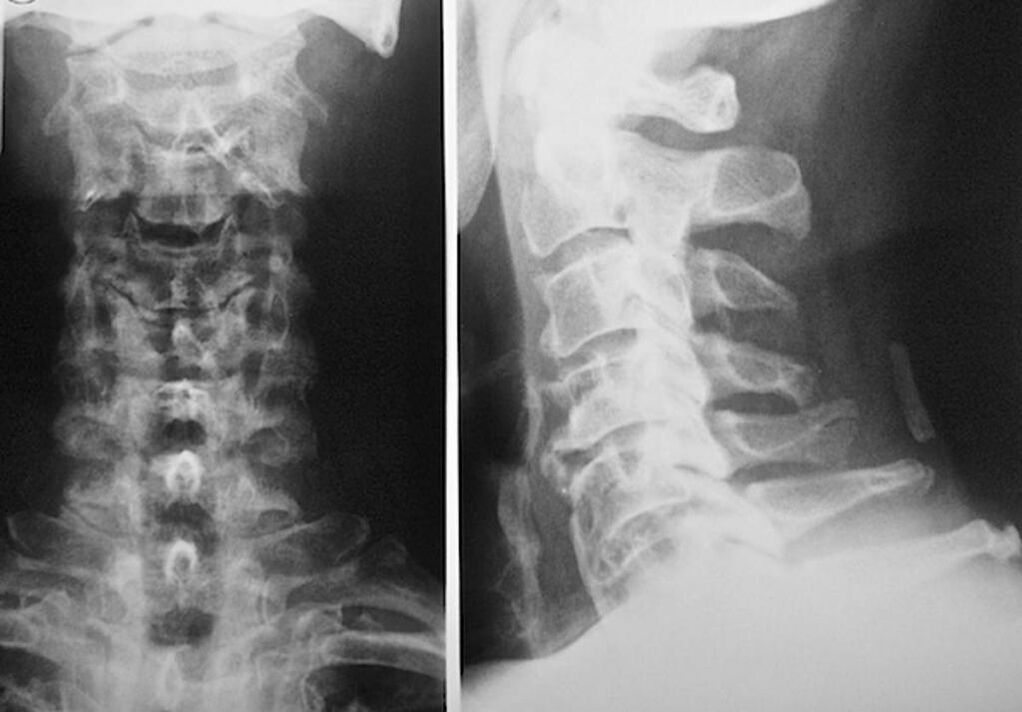

Na diagnostiku a presné posúdenie stavu medzistavcových platničiek sa používajú tieto výskumné metódy:

- Rádiografia.

- CT vyšetrenie.

- Magnetická tomografia.

- Ultrazvukové skenovanie krčných ciev.

Každý z nich je úplne bezpečný pre zdravie a nepredstavuje žiadnu hrozbu nadmernej expozície. Diagnózu osteochondrózy krčných stavcov, ktorej liečba sa bude vykonávať po celý zvyšok života, je možné vykonať po jednoduchom vizuálnom vyšetrení. To môže ľahko urobiť každý ortopéd. Výnimkou je prvá fáza ochorenia, keď nie sú zaznamenané žiadne viditeľné patológie krčnej oblasti.